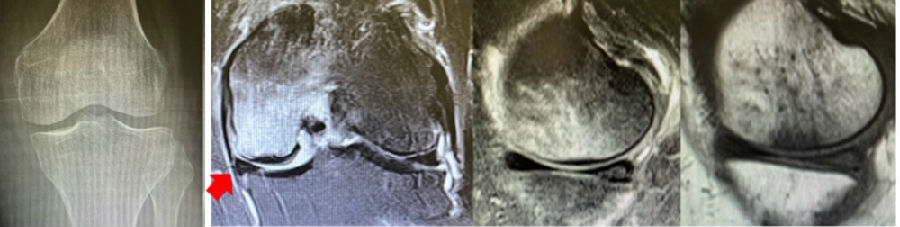

a.患者,59岁女性,AP侧位片显示SONKⅠ期,FTA<180°;b.MRI T2显示病变深度<20mm,患者出现症状1年后保守治疗;c.75岁女性,X线显示SONKⅠ期,FTA>180°;d. MRI T2显示病变深度>20mm,患者于症状出现后11周行手术治疗

病例:女,65岁,主诉左膝关节内侧疼痛2月余。2017年11月X光未见左膝骨质异常。MR见股骨内侧髁骨坏死,半月板相对突出百分比(RPE)28.3%,合并内侧半月板后根部撕裂,矢状位病变区域前后径为11.67mm,关节线会聚角2.68°

2018年2月复查MR见骨髓水肿明显吸收,坏死灶边界清晰,半月板相对突出百分比(RPE)28.92%

2018年6月复查MR见骨髓水肿基本完全吸收,坏死区修复良好,半月板相对突出百分比(RPE)38.54%,患者临床症状消失。

提示坏死好转了,但半月板突出进展了,膝关节的退变加重了。